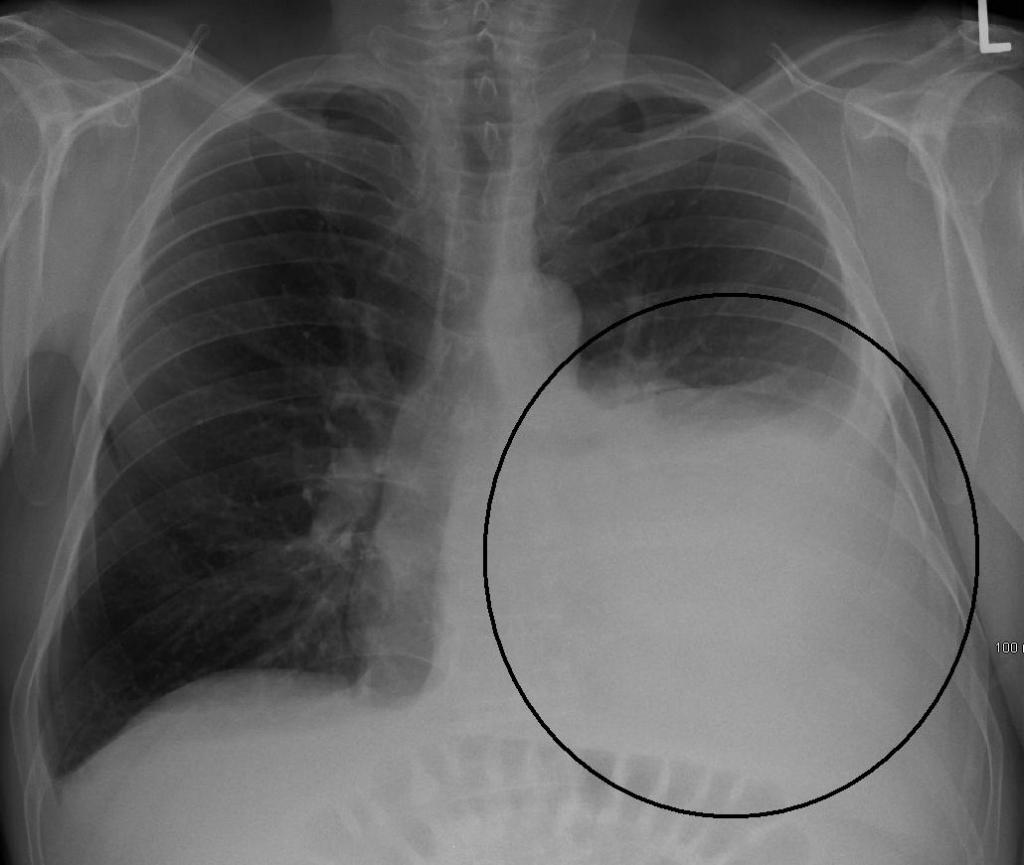

En cas de pneumonie, le plan des mesures médicales repose sur la présence de complications, car elles peuvent être graves et mettre le patient en danger de mort. Il peut s'agir d'un choc septique, d'un œdème pulmonaire ou d'une insuffisance respiratoire. Sur la base de la présence de complications, la gravité de la maladie est déterminée et la question de la nécessité d'une hospitalisation est tranchée.

- deux ou plusieurs lobes sont affectés sur une radiographie;

- Degré sévère. Le patient présente des symptômes d'intoxication: la température corporelle est supérieure à 38 degrés. Une insuffisance respiratoire est observée, l'hémodynamique est perturbée. Avec des complications, un choc septique peut être diagnostiqué. Dans KLA, la leucopénie ou la leucocytose. L'infiltration est bilatérale, avec une augmentation rapide dans la zone touchée.